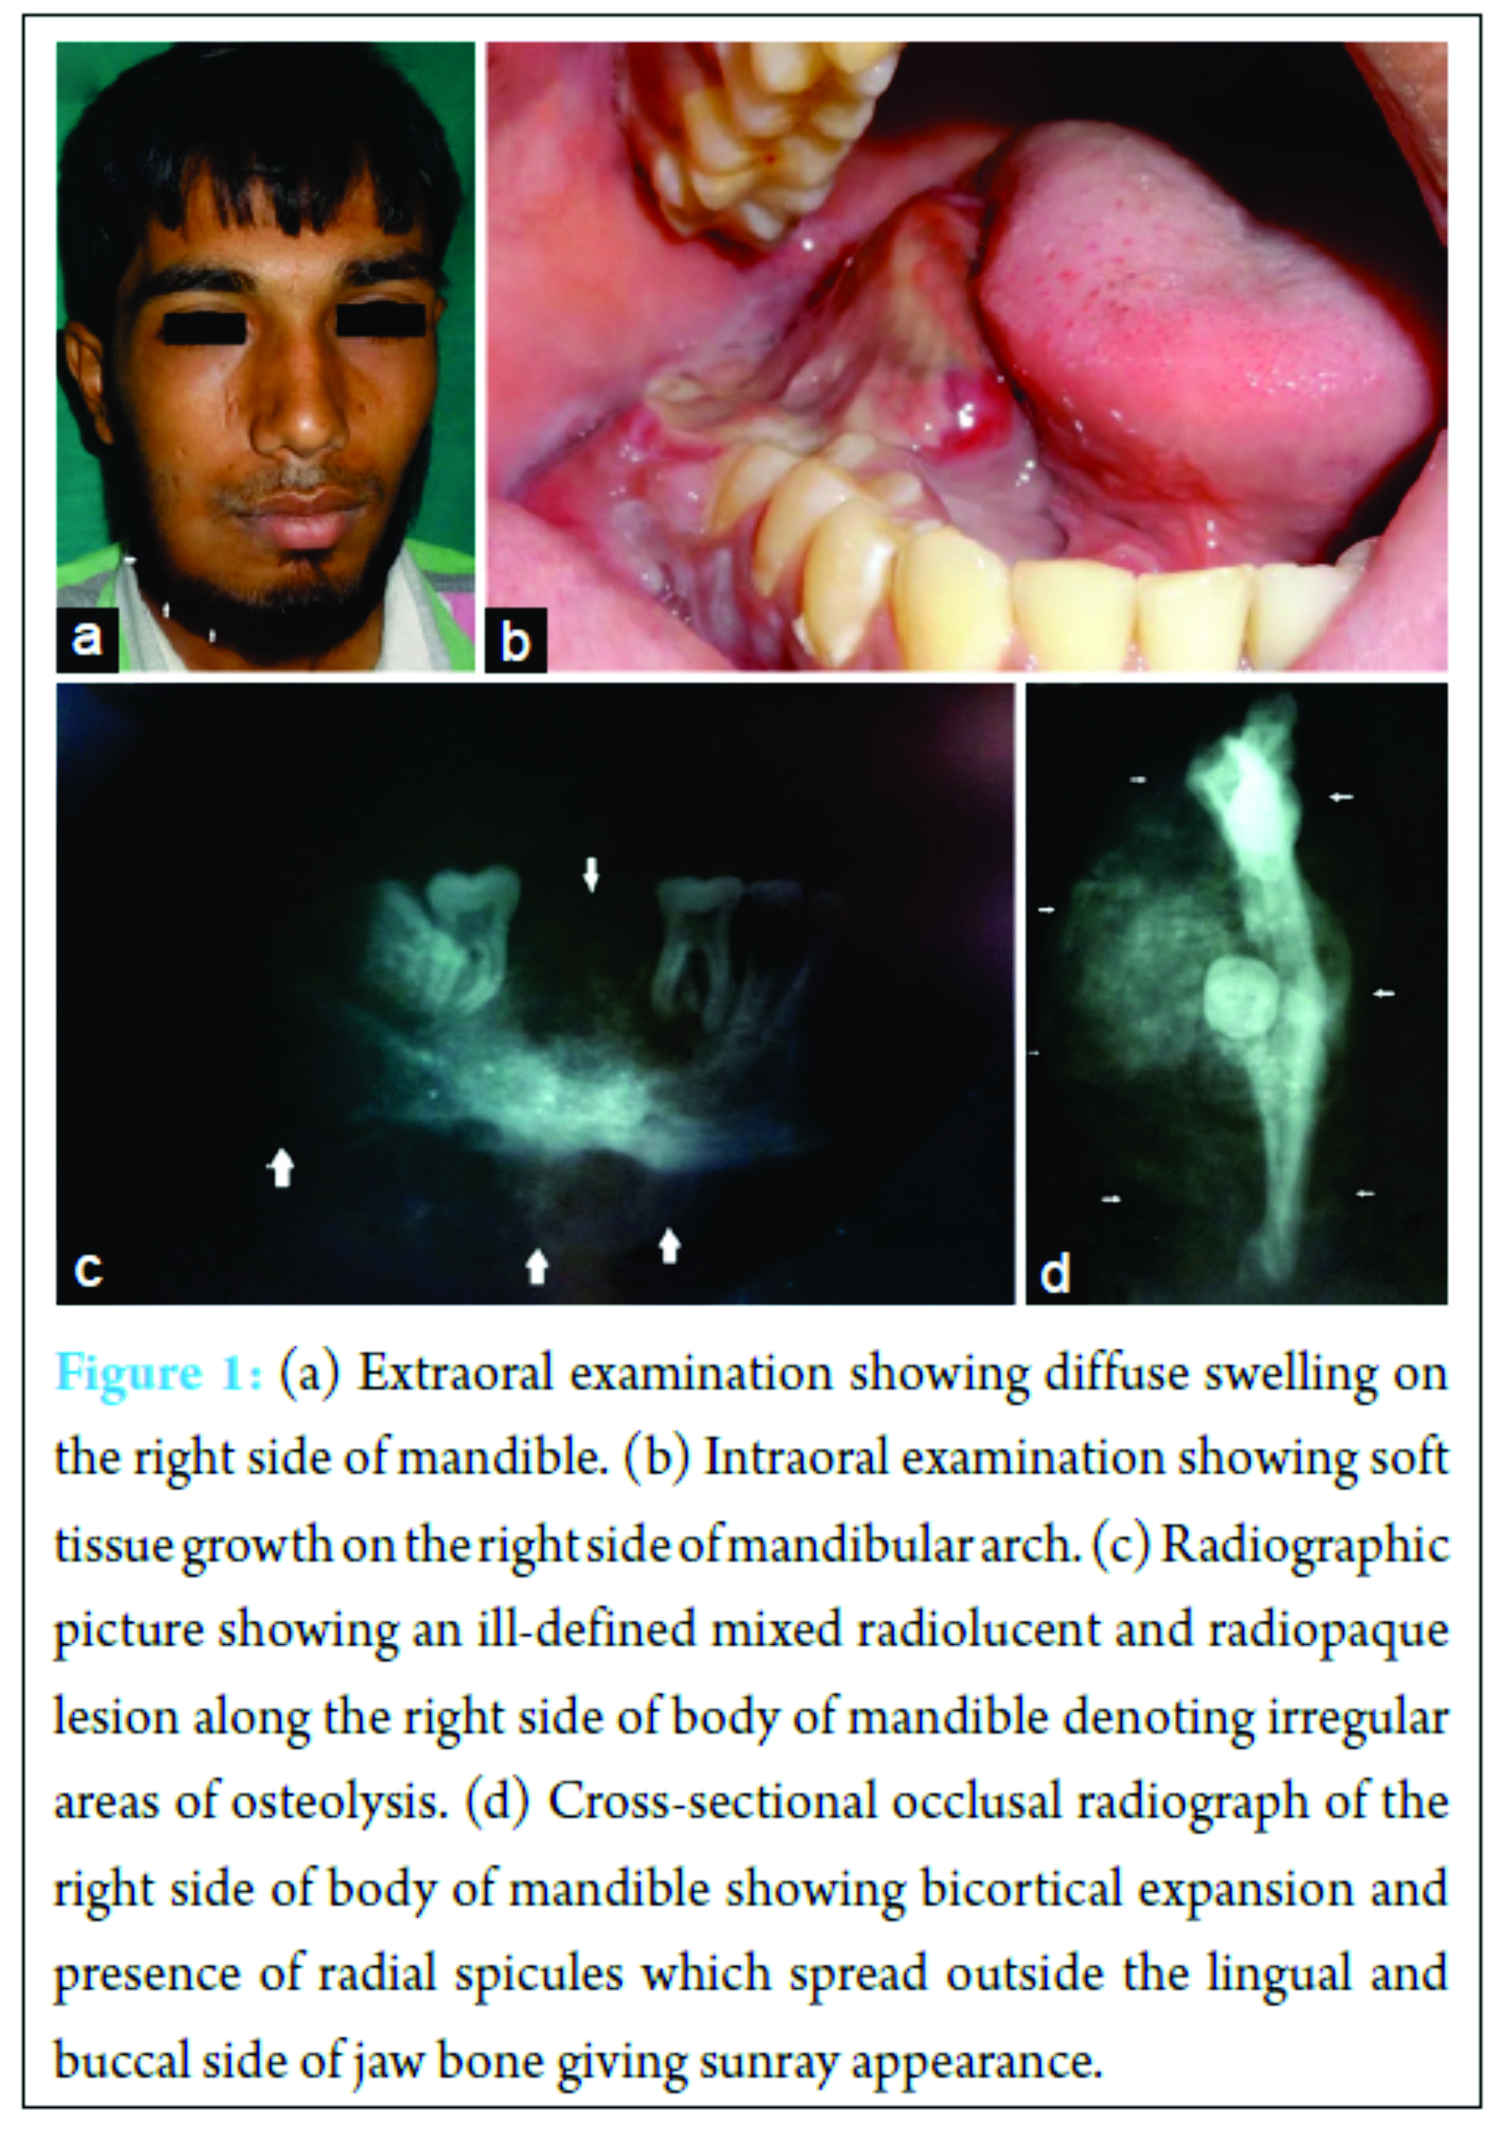

A 21-year-old male reported with a diffuse swelling and pain in the lower right posterior region of jaw for 4 months. Pain was dull and intermittent with increase in difficulty during eating and speech. The patient gave a history of extraction 1 month before for the same complaint, but there was no relief. After 2 months, growth appeared intraorally. Medical history was non-contributory. Extraoral examination revealed a diffuse swelling on the right side of mandible, extending anteroposteriorly from 1 cm behind angle of mouth to angle of mandible. Superoinferiorly, 2 cm below line drawn from angle of mouth to tragus of ear to 4 cm below lower border of mandible roughly measuring around 5 cm × 4 cm in size. Skin over swelling appeared normal on inspection and firm and tender on palpation. Right submandibular lymph node was palpable, enlarged, firm to hard, and fixed (Fig. 1a). Intraoral examination revealed a soft tissue growth along the right side of mandibular arch. It extended from first premolar to retromolar region causing obliteration of buccal and lingual vestibule. Overlying mucosa was red. Surface appeared smooth with areas of depression at places (Fig. 1b).

Radiographic evaluation included panoramic radiograph, occlusal radiograph, and cone beam CT. Panoramic radiograph revealed an ill-defined mixed radiolucent and radiopaque lesion along the right side of body of mandible denoting irregular areas of osteolysis (Fig. 1c). The cross-sectional occlusal radiograph of the right side of body of mandible showed bicortical expansion and presence of radial spicules which spread outside the lingual side of jaw bone giving sunray appearance (Fig. 1d). Aspiration was done which gave yellowish viscous blood tinged fluid. Based on clinical and radiological findings, the provisional diagnosis of malignancy of right side of the mandible, hemangioma, and osteosarcoma was given. The incisional biopsy revealed osteoid tissue with irregular trabeculae with osteoblasts which were large round to oval, epithelioid in appearance with hyperchromatic nucleus and prominent nucleoli and occasional atypical mitoses. Intertrabecular areas showed solid cellular stroma. As the biopsy was incisional, tumor border cannot be traced. Hence, the diagnosis was given as aggressive osteoblastoma/Osteoblastoma like osteosarcoma(Fig. 3b). Lesion was excised. Grossly, there was extensive soft tissue destruction with an associated soft tissue mass (Fig. 2a). The histopathology revealed abundance of osteoid and tumor bone without osteoblastic rimming suggestive of osteoblastic osteosarcoma (Fig. 3c). Other areas showed fibrous spindle cell areas where osteoid or tumor bone was scarce i.e. (fibroblastic/fibrohistiocytic type Fig. 3a). At focal places, vessels were numerous, dilated and proliferating giving a haemangiopericytomatous appearance (Fig. 3d) (Staghorn type appearance).